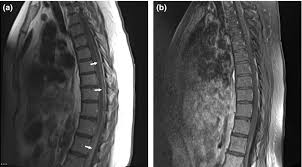

Dural And Leptomeningeal Spine Metastases Of Breast Cancer

Leptomeningeal Metastases Radiology Reference Article Radiopaedia Org